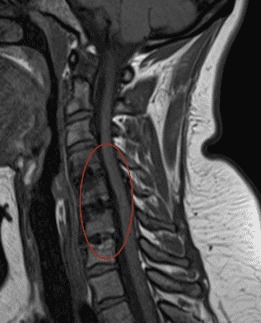

-Случай Nº 17635

Грыжа или протрузия межпозвоночного диска на уровне шейного отдела может задеть нервные корешки или спинной мозг. В этом отделе позвоночника очень мало свободного пространства для дисков, отсюда более частое возникновение грыж с компрессией нервных корешков или спинного мозга.

Если есть подозрение на повреждение нервного корешка, проводится магнитно-резонансная томография (МРТ) или компьютерная томография (КТ). Если речь идет о грыже диска или стенозе позвоночного канала, решение о лечении основывается на клинических данных и на осмотре пациента.